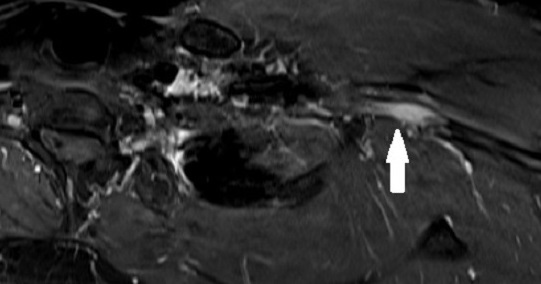

A 67-year old woman with chronic hypertension, hyperlipidemia and diabetes mellitus non-compliant to medication presented with a 10-day history of recurrent visual phenomena in the left visual field. She described stationery multi-coloured flashing lights which decreased in intensity, brightness and size after 3 minutes. She was alert and conscious during attacks. There was no limb jerking. Neurological examination was normal with no visual field defect. Capillary glucose was 28.1 mmol/L, Hba1c 9% and B-hydroxybutyrate < 0.1. She was treated with actrapid 8 units, glipizide 5 mg BD and empagliflozin 12.5 mg OM. Interictal electroencephalogram was normal with no epileptiform activity. Brain magnetic resonance imaging revealed restricted diffusion in the right occipital cortex with corresponding cortical thickening and increased FLAIR signal with subtle hypodensity on GRE sequence. Her visual symptoms improved dramatically with hydration and diabetic control. She was treated with a short course of keppra. One month later repeat MRI brain showed resolution of the DWI and FLAIR abnormalities.

Conclusions:

Visual hallucinations are an uncommon but well recognised and fully reversible complication of HHS. Clinicians should not forget HHS in the workup of occipital lobe.

Initial dwi

D